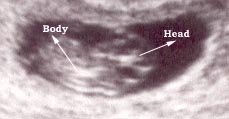

Photo Two

This is a nine weeks pregnancy as seen using a vaginal probe.